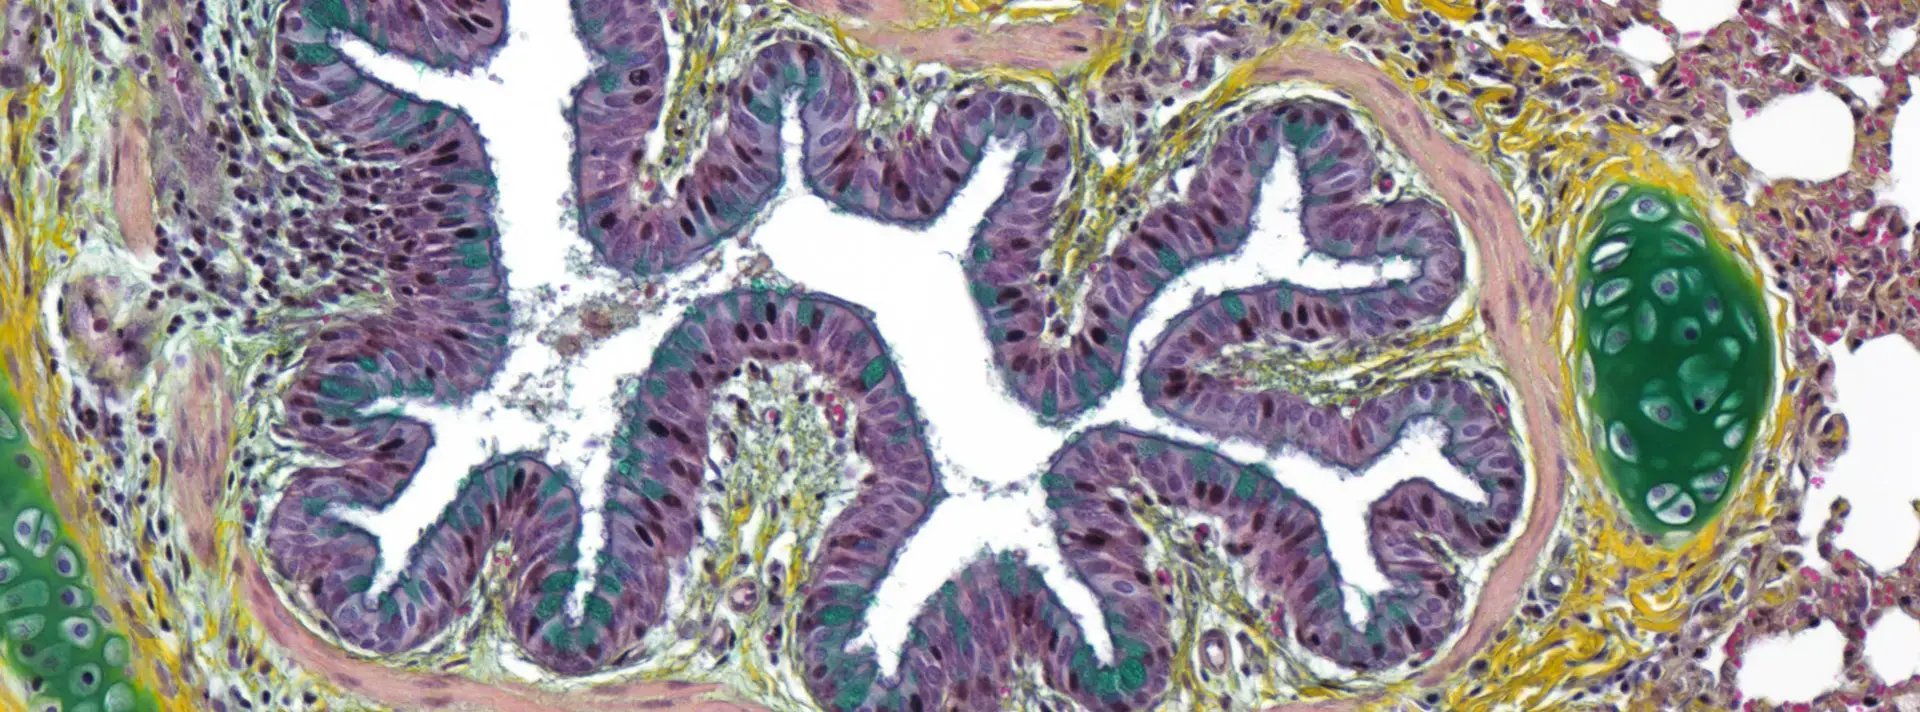

Necropsy Mastery and Processing Expertise

The foundation of reliable results begins at necropsy. Exceptional pathologists understand that errors at this stage cannot be corrected downstream, potentially requiring expensive, time-consuming study repetition. This expertise extends to understanding biomaterial processing requirements: knowing whether a device component can withstand paraffin processing or requires plastic embedding, testing processing parameters to prevent melting or crushing delicate test articles, and ensuring that tissue harvesting preserves both device integrity and biological response.